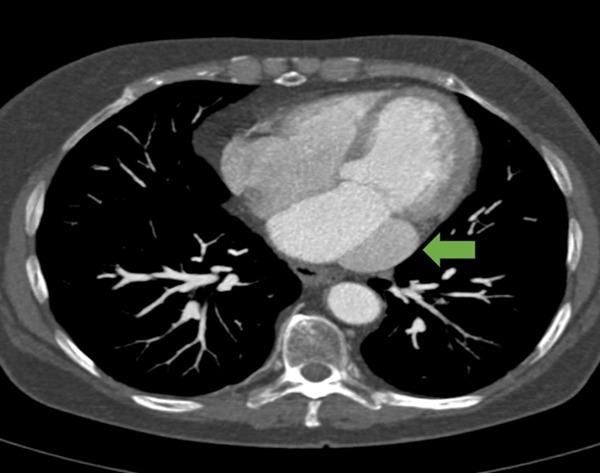

Persistent left superior vena cava (PLSVC) is a rare vascular congenital anomaly yet the most common for the thoracic venous system. Usually asymptomatic, PLSVC is commonly diagnosed when echocardiography or other cardiovascular imaging is performed. Due to venous drainage abnormality, PLSVC is frequently associated with other anomalies of the intrinsic heart's conduction system, leading to tachy- or brady- arrhythmias. We present the case of a patient with 20 years history of supraventricular rhythm disorders diagnosed with isolated PLSVC. Furthermore, we discuss the diagnostic approach providing insights into four-dimensional echocardiography (4DE) evaluation for PLSVC diagnosis, assuming that there is a direct correlation between coronary sinus dilatation caused by abnormal venous return and supraventricular rhythm disorders. We highlight that correct understanding of the pathophysiology of PLSVC will lead to a reduction in unnecessary and potentially harmful testing, to a shorter diagnostic time and to a financial resource saving, as a whole.

永存左上腔静脉(PLSVC)是一种罕见的血管先天性异常,但却是胸静脉系统中最常见的。PLSVC通常无症状,常在进行超声心动图或其他心血管成像检查时被诊断出来。由于静脉引流异常,PLSVC常与心脏固有传导系统的其他异常相关,导致快速或缓慢心律失常。我们报告一例有20年室上性节律紊乱病史的患者,诊断为孤立性PLSVC。此外,我们讨论了诊断方法,假设异常静脉回流引起的冠状窦扩张与室上性节律紊乱之间存在直接关联,从而深入了解四维超声心动图(4DE)对PLSVC诊断的评估。我们强调,正确理解PLSVC的病理生理学将减少不必要的、可能有害的检查,缩短诊断时间,并节省整体财政资源。